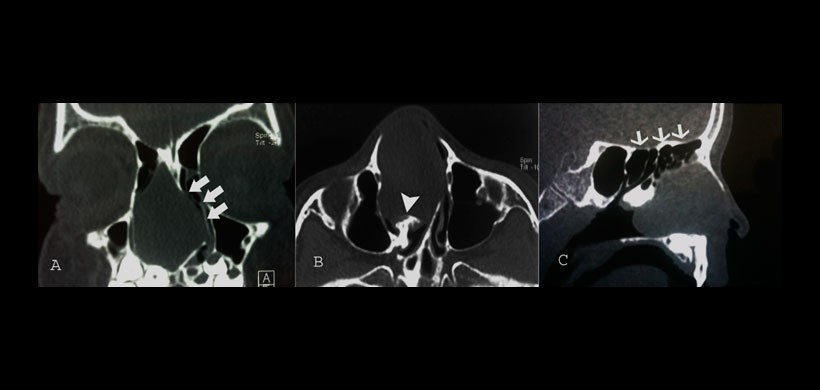

Posterior al examen clínico se realizó una tomografía computarizada de alta resolución, la cual mostró una lesión isodenza de limites definidos, al parecer originarios de la región del cornete medio y era compatible con un mucocele de cornete medio

(Figura 1A y 1B), sin embargo la lesión se limita solo en zona de senos paranasales y no involucra la base de cráneo (Figura 1C).

Figura 1: Tomografía computarizada de un mucocele de fosas nasales: A, corte coronal, B corte axial y C, corte sagital